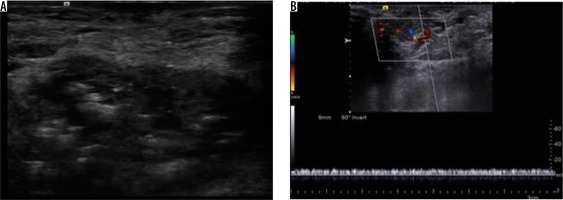

Figure 9

Haemangioma – greyscale ultrasound image (A) shows a well-defined hypoechoic lesion with hyperechoic foci associated with posterior acoustic shadowing. Colour and spectral Doppler examination (B) of the same lesion demonstrates venous flow within the lesion. The findings were suggestive of haemangioma